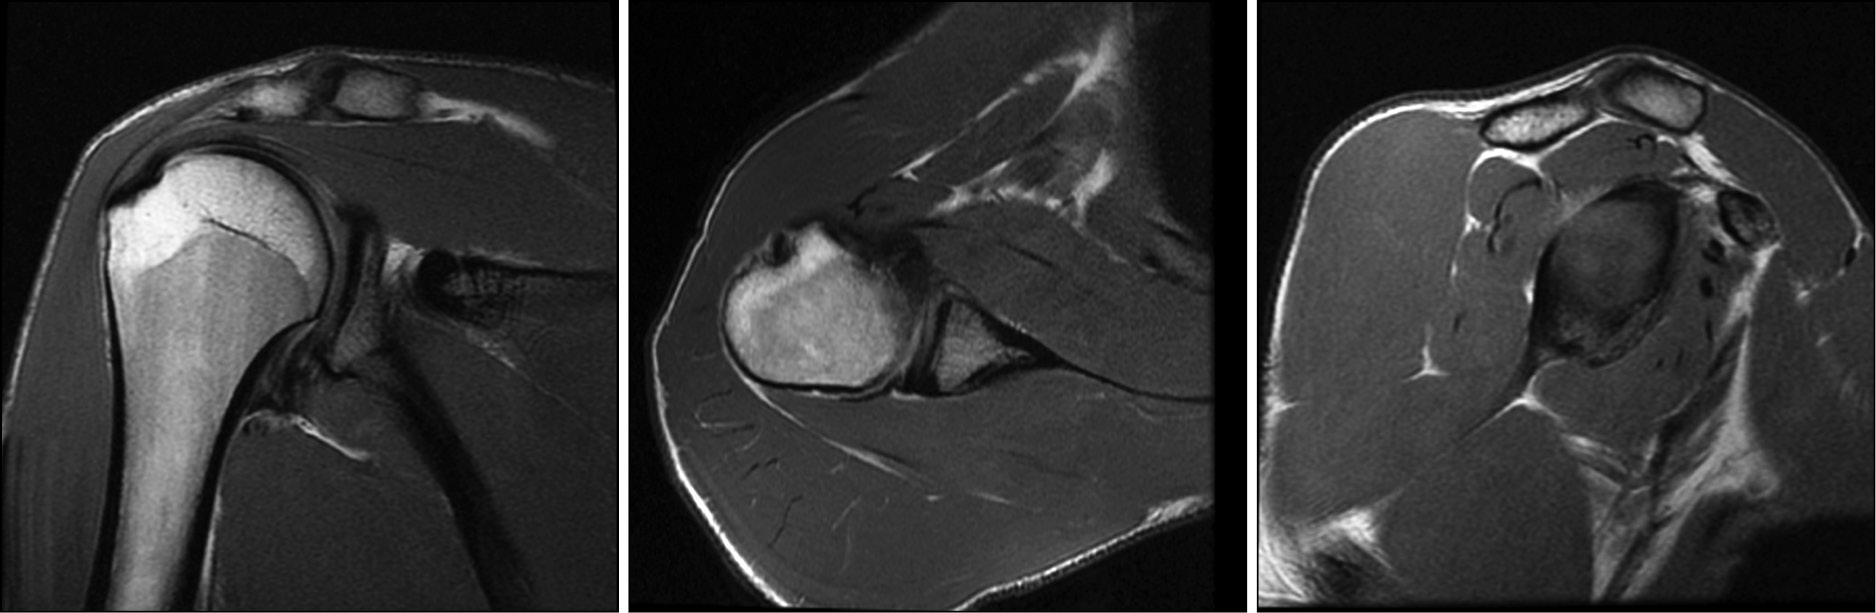

All patients underwent a thorough preoperative clinical examination, magnetic resonance imaging (Fig. 1), computed tomography (Fig. 2), and radiography of the shoulder joint in the antero-posterior, West Point and Stryker views (Fig. 3) [17, 24].

Fig. 1. Magnetic resonance imaging of the shoulder joint with glenoid deficiency.

When implementing the diagnostic technique, they considered defects in the articular surface of the scapula, options for its compensation, and the shape of the coracoid process. This was done to determine the level of osteotomy and fixation in the anterior–inferior part of the scapular cavity (Fig. 1) [21, 24].